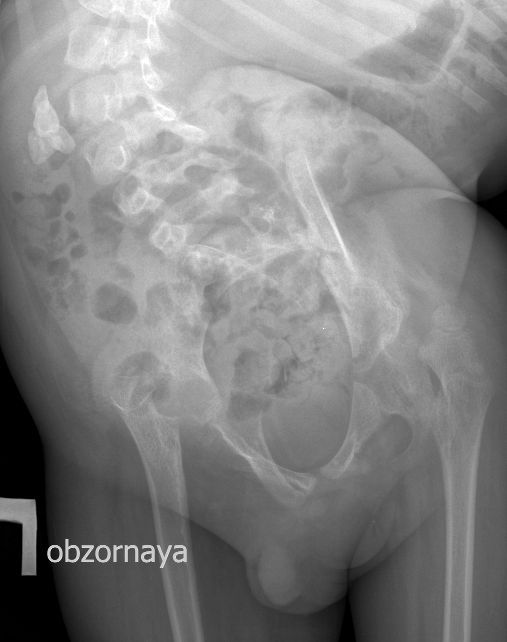

Для того, чтобы продемонстрировать степень ортопедических проблем и облегчить задание (или усложнить :) ) добавляю обзорную рентгенограмму брюшной полости

DX0001.jpg

Нейрогенный мочевой пузырь (?), МКБ, конкремент мочевого пузыря, двухсторонний мегауретер, конкремент правой почки.

Если честно, и я изначально не совсем понял, где находится конкремент (а это конечно же конкремент), локализованный на урограммах. При первичном исследовании на УЗИ его я не видел (либо он спрятался за тенью конкремента мочевого пузыря, либо я обрадовался редкой находке конкремента такого размера в мочевом пузыре - 2.5 см, и не посмотрел что ниже). Тем не менее при ретроспективном анализе архивированных сонограмм, как мне кажется, он попал в один из сканов, м.б. не совсем чётко.

И всё -же, где конкремент :?:

Возможно, в дивертикуле либо в нижней трети мочеточника..